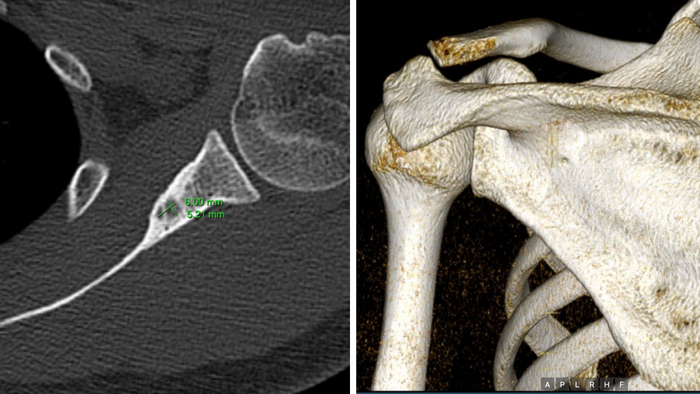

Tại đây, sau nhiều xét nghiệm, anh được chẩn đoán u xương dạng xương (osteoid osteoma) – một khối u lành tính kích thước nhỏ (khoảng 1cm) nhưng nằm sâu trong xương, ở vị trí khó tiếp cận. Các bác sĩ cho biết có thể điều trị nội khoa trước, nếu không đáp ứng thì phải phẫu thuật mở – một lựa chọn tiềm ẩn nhiều rủi ro và thời gian hồi phục kéo dài. "Nghe đến phẫu thuật, em lo lắm. Vì vị trí u phức tạp, nguy cơ ảnh hưởng vận động vai rất cao," – anh nói.

U lành tính kích thước nhỏ (khoảng 1cm) nhưng nằm sâu trong xương, ở vị trí khó tiếp cận